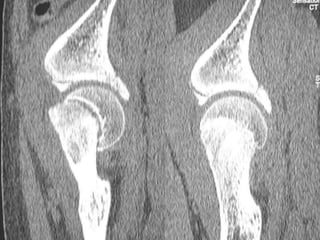

 CT SCAN-

Accurately measures extent of epiphyseal displacement & angulation.